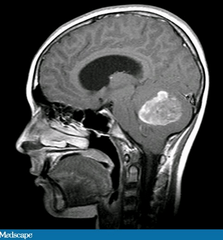

In our age of medical technology, we can quickly localize and identify tumors with a quick brain scan (see image at right). However, in 1905 there was no magnetic resonance imaging to allow Jacobi to see inside her brain (though people were quite creative). Yet, with careful consideration of her symptoms, this clever woman unraveled her own internal mystery. Although we cannot confirm that she did indeed have a cerebellar meningioma, the symptoms she describes align perfectly with recent accounts of cerebellar tumors, or even the complete absence of a cerebellum.